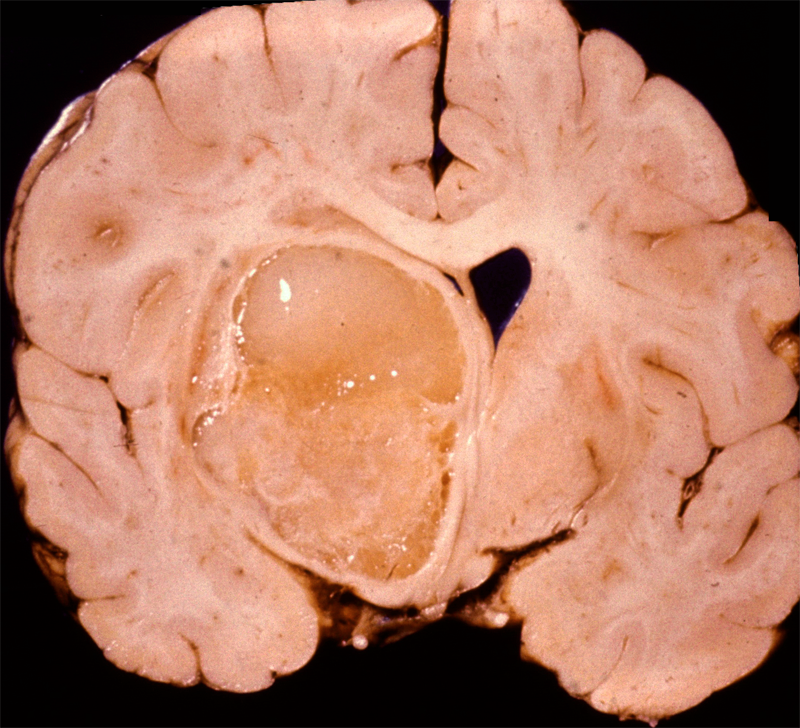

Cysticercosis is the most common parasitic infection and neurocysticercosis is the most common cause of secondary seizures worldwide. Cysticercosis is caused by ingestion of water, vegetables and other foods fecally contaminated by eggs excreted by carriers of the pork tapeworm, Taenia Solium. In the intestine, the eggs transform into oncospheres which penetrate the intestinal wall, enter the circulation and lodge in the brain, eyes, muscles and other tissues. There, oncospheres develop into cysticerci. The same sequence occurs in pigs, which are the intermediate host of T. solium. In pigs, cysticercosis affects primarily muscles. After consumption of pork containing cysticerci, scolices attach to the small intestinal wall and develop into adult worms. This condition is called intestinal taeniasis. Eggs or proglotids of the adult worms are then shed in the feces, contaminating the environment.